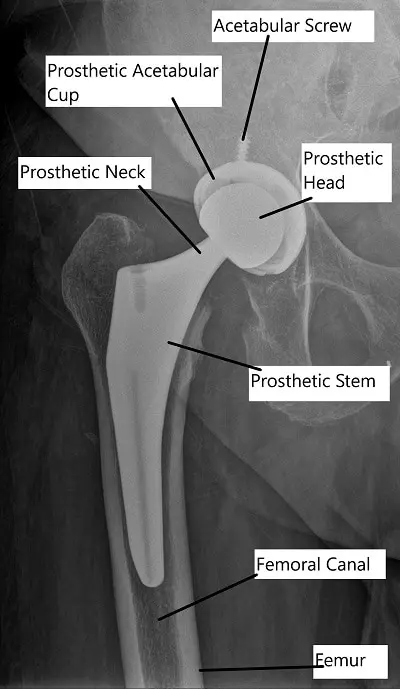

X-ray showing Total Hip Replacement in AP view.

Anterior hip replacement surgery requires general anesthetic – once this has been administered, a surgical approach using the anterior skin directly overlying the hip is used. The surgeon then parts the muscles in this area without cutting them and exposes the hip capsule. This will then be opened and the arthritic femoral head will be removed. The acetabulum will be prepared for its replacement component by grinding away the arthritic bone with a special tool, and once it is placed in position, it may be held in place with one or more bone screws.

Once retractors are placed and visualization of the proximal femur is adequate, other special tools can be used to determine the correct size of replacement component for each patient. X-rays are used to help determine the appropriate position and size of the implant intraoperatively. It is also used to help the surgeon determine that the length of the leg is equal to the other side once the right size component has been selected.